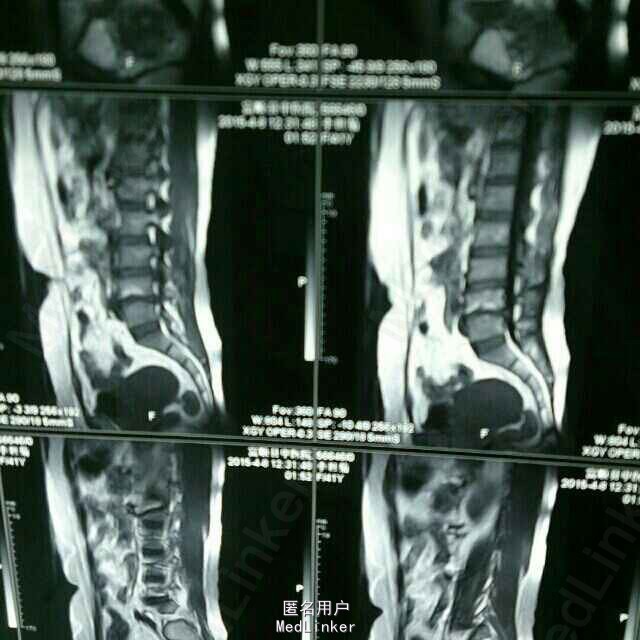

门诊病例分享,又一例微创术后终板炎

腰骶部疼痛两年,间歇性跛行1年余,自诉一个月前行腰椎微创手术,射频消融。 体检发现四肢肌力正常,深浅反射正常,无特殊发现。暂无血液检查。影像学检查发现腰椎骨质破坏,终板炎,腰椎管狭窄。诊断为:腰椎管狭窄症;终板炎。处理:入院手术。 讨论,脊柱微创术后终板炎还真的不少见,前面我也发了两个颈椎的病人终板炎的病例。PS,希望疼痛科,康复科在做这类微创的时候把握好手术指症。欢迎大家评论讨论。